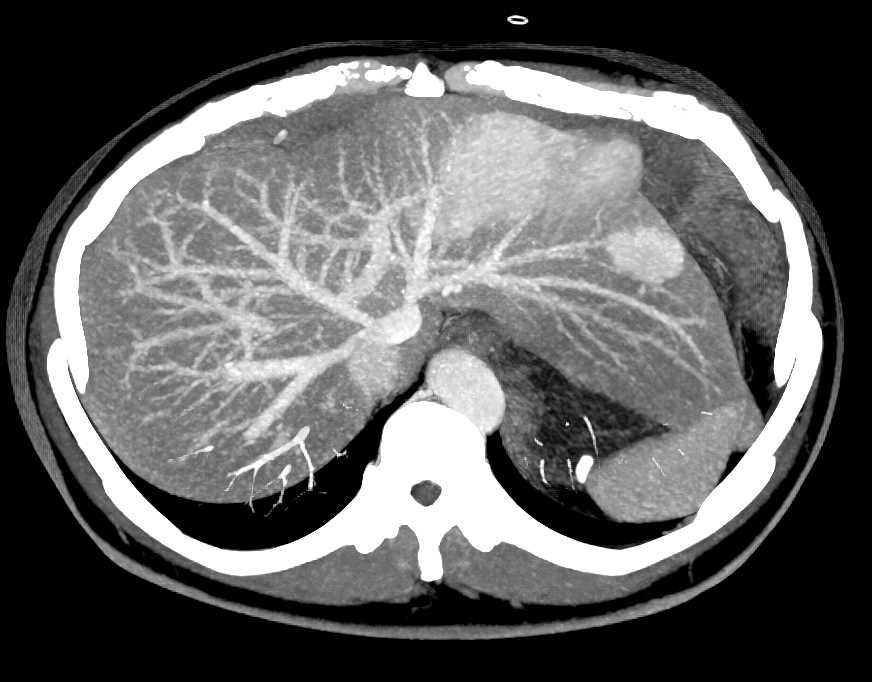

CT

要看清楚我们,CT检查是更清楚的。在CT下的我们,也是边界清楚的,呈低密度的肿块。大约10%的我们,可以同时发现里面有一些钙化灶。